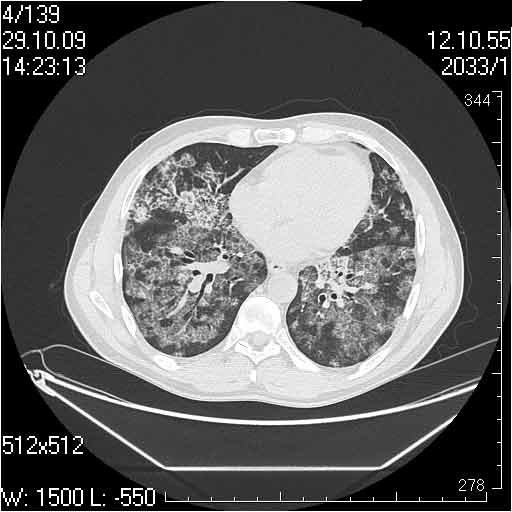

Случай №1

Женщина 50 лет.

Случай 1: изменения характерны для интерстициальной пневмонии (IIP/UIP idiopathic interstitial pneumonia/usual interstitial pneumonia); говорить о конкретной форме без открытой биопсии затруднительно.